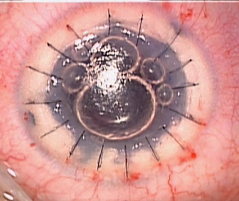

- B) Implante de Segmento(s) de Anel Intra-corneano no Ceratocone

Perguntas e respostas sobre implante de anel de Ferrara®.

Dr. Gustavo Bonfadini, esclarece sobre as dúvidas da cirurgia de anel intracorneano, as indicações, benefícios e cuidados no pós-operatório:

Esta técnica pode evitar o Transplante de Córnea que é um procedimento complexo devido ao risco de rejeição.

Um aspecto importante deste tratamento, é que esta técnica é reversível, pode ser ajustada em caso de correção inadequada. O anel poderá ser removido em qualquer época. A cirurgia é realizada sob anestesia local. A cirurgia é rápida e indolor, permitindo assim uma recuperação rápida e a volta do paciente às atividades normais em pouco tempo.

1) O que é e qual objetivo do Segmento de Anel (anel intra estromal)?

O anel intracorneano (Kerarings ®, Anel de Ferrara ® ou Intacs ®) é uma órtese transparente composto de um material inerte e biocompatível ao olho, de formato semicircular, de espessuras e diâmetro variáveis.

O objetivo do anel é regularizar e diminuir a curvatura corneana, e consequentemente melhorar a visão. Além disso, esse dispositivo é capaz de diminuir ou corrigir os erros de refração da Córnea de um paciente com Ceratocone.

2) Quando o implante de Anel de Ferrara é indicado?

Segundo o especialista nesta cirurgia, Dr. Gustavo Bonfadini, o implante é indicado para os casos de Ceratocone em qualquer faixa etária, que têm baixa visão com óculos de grau ou lentes de contato ou ainda intolerância às lentes de contato, e que ainda não têm indicação para transplante de córnea.

A melhor indicação de tratamento com uso do anel corneano é no estágio moderado do Ceratocone, pois tem como objetivo tentar melhorar a estrutura da córnea e regularizar as deformações corneana, e tentar corrigir ou diminuir os erros de grau associados a esta córnea. O anel intracorneano é fabricado a partir do PMMA (polimetilmetacrilato), material comprovadamente inerte, biocompatível, não havendo risco de rejeição, pois este material é utilizado há décadas na fabricação de implantes intra-oculares.

3) O Anel pode ser implantado em todos os casos de Ceratocone ?

Esta é uma pergunta muito frequente, porém nos casos de Ceratocone avançado, com opacidade, cicatriz corneana e em córneas muito finas há contra-indicação ao uso do anel. Assim, uma avaliação oftalmológica completa será necessária, incluindo biomicroscopia (análise da transparência), Topografia de córnea (análise da superfície corneana) e Paquimetria (medida da espessura corneana).

4) Como é feito o implante do Anel de Ferrara?

Dr. Gustavo Bonfadini, explica que é aplicada anestesia local por meio de colírio, sem necessidade de internação. Atualmente este procedimento é idealmente realizado por meio de um Laser de Femtosegundo. Com o uso do Laser, não há corte com bisturi, fazendo com que a incisão seja criada a partir de uma fotodisrupção (separação) das lamelas da córnea, confeccionando assim um túnel no interior da Córnea. Exatamente conforme planejado pelo cirurgião especialista em córnea, conferindo uma maior previsibilidade e eficiência no implante do anel.

Em seguida, acontece o implante de 1 ou 2 seguimentos de anel. A cirurgia dura em média 30 minutos. Os segmentos vão tentar o aplanamento do ápice da córnea tentando deixá-la o mais próximo do natural. Esta técnica é reversível, sem danos para a córnea, e não é uma técnica refrativa, ou seja, o paciente deverá utilizar óculos ou lente de contato após a cirurgia de Ceratocone.